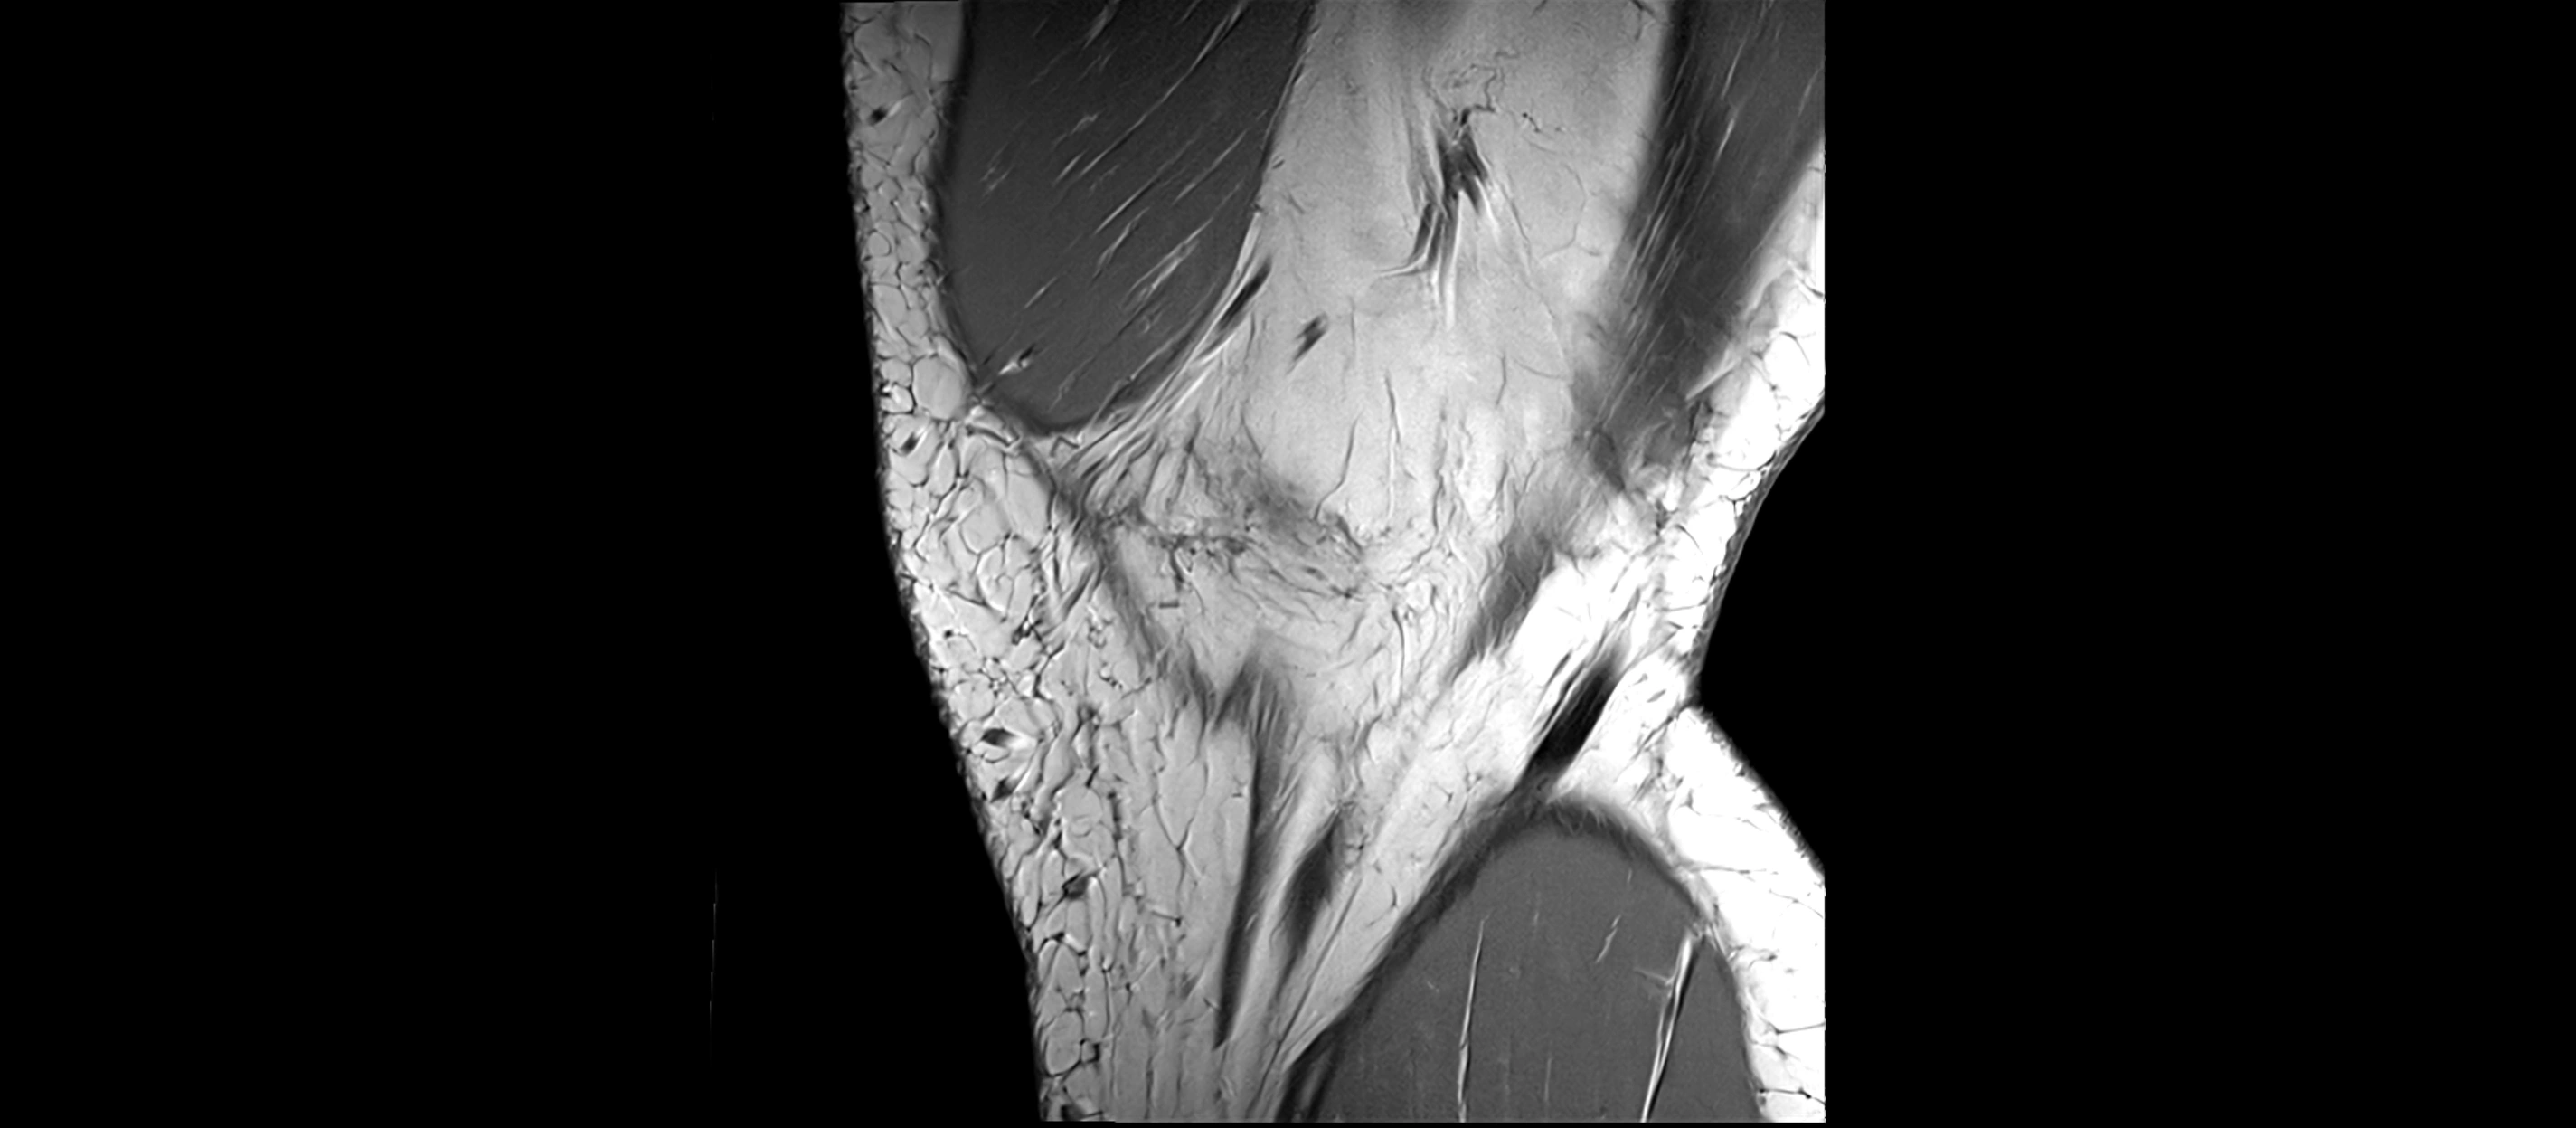

MRI images

image